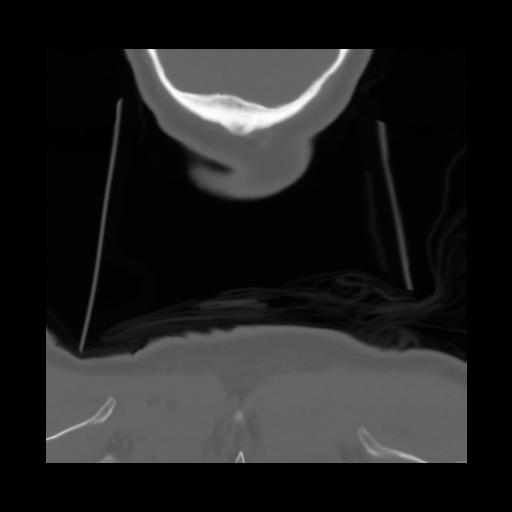

13 P.BLANDAS,,Coronal,2.000,P.BLANDAS,Coronal,